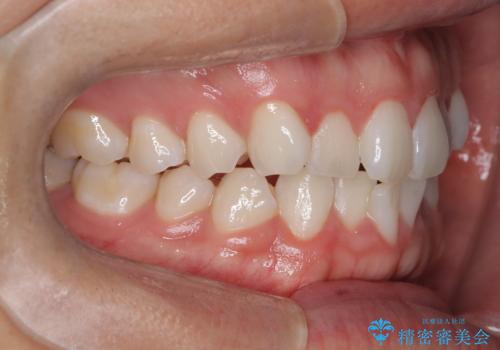

歯のデコボコを治したい|インビザラインで綺麗な歯並びに!|矯正期間は6ヵ月!

- 歯のデコボコが気になるを主訴に来院された患者様です。

インビザラインで歯は抜かずに非抜歯でデコボコを改善しました。

インビザラインで叢生の改善を行いました。

歯は抜かずに、拡大と少しのIPRで並べました。

矯正期間は半年です。

綺麗な歯並びを手に入れ大変ご満足していただきました。